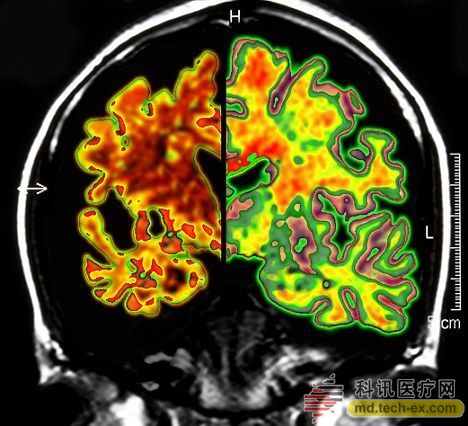

在手術(shù)中,所有病患的腦部將被植入電極,這些電極與一個類似起搏器的裝置相連接,能夠每秒鐘發(fā)出130次電脈沖。羅森博格表示,病人并不會感受到電脈沖的存在。 研究人員表示,所有接受臨床試驗的病人同時都會被植入這個“起搏器”裝置。其中,一半病人的“起搏器”將于手術(shù)后兩周開啟,而另一半病人的要在手術(shù)后一年才會開啟。目前,參加臨床試驗的病人和醫(yī)生并不知道分組情況。 其實早在2010年,加拿大就已經(jīng)對這種大腦“起搏器”展開臨床試驗。當時,有6名輕微老年癡呆癥患者參加。當時的試驗結(jié)果顯示,在13個月的觀察期中,這些病患的葡糖糖代謝速度持續(xù)上升,這也就說明他們的大腦神經(jīng)元正在工作。而在同時期內(nèi),大部分老年癡呆癥患者的葡萄糖代謝水平則是在不斷下降。